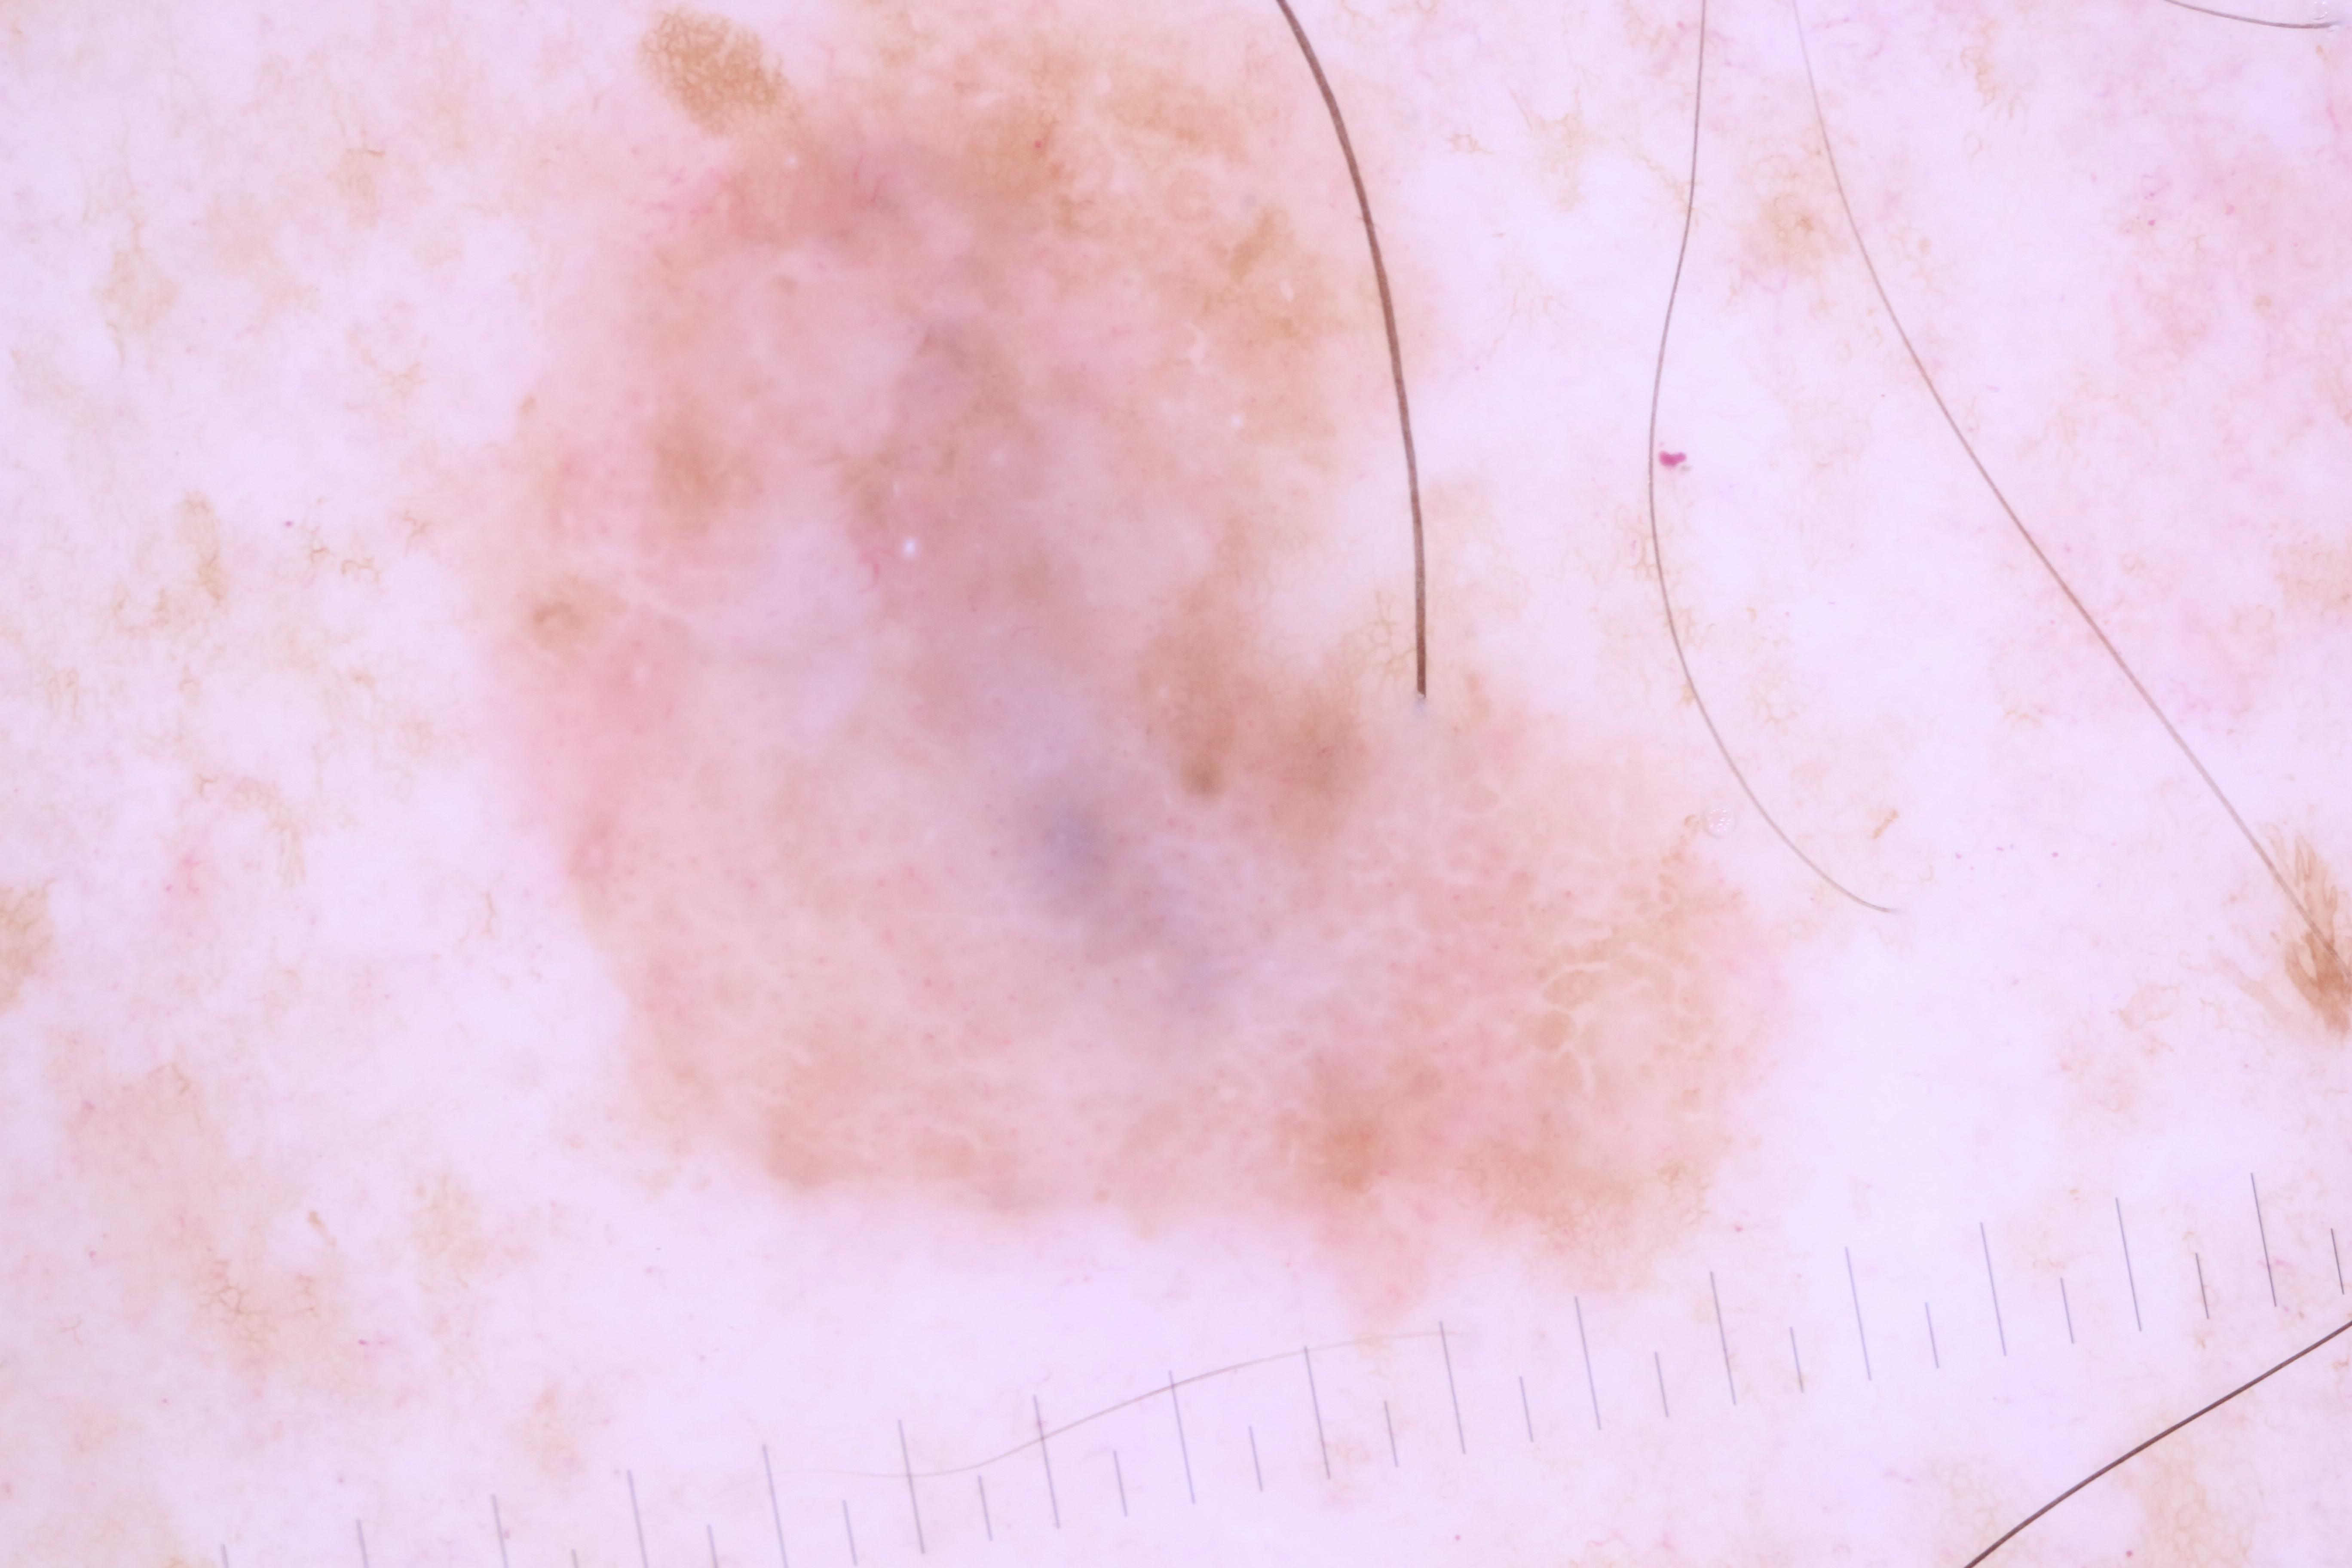

{

"age_approx": 55,

"anatom_site_general": "lower extremity",

"concomitant_biopsy": true,

"dermoscopic_type": "contact polarized",

"diagnosis_1": "Malignant",

"diagnosis_2": "Malignant melanocytic proliferations (Melanoma)",

"diagnosis_3": "Melanoma in situ",

"diagnosis_confirm_type": "histopathology",

"family_hx_mm": true,

"image_type": "dermoscopic",

"mel_thick_mm": "0.00",

"melanocytic": true,

"patient_id": "IP_6476463",

"personal_hx_mm": false,

"sex": "female"

}